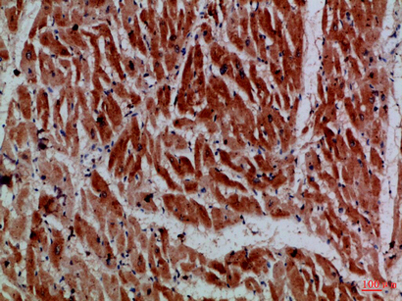

Recomended Dilution IHC-p 1:50-200, ELISA 1:10000-20000

Subcellular Location Cytoplasm, myofibril. Thick filaments of the myofibrils.